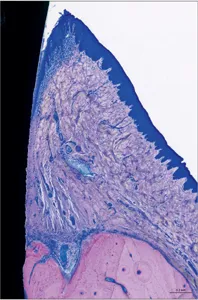

The periodontium comprises the tissues supporting the teeth: the tooth-facing part of the gingiva, the root cementum, the periodontal ligament, and the part of the alveolar process that lines the tooth socket, termed alveolar bone (Schroeder and Listgarten 1997) (Figs 1 to 5).

Fig 1 Photomicrograph. Tooth with a healthy periodontium. Supporting tissues of the tooth consisting of the root cementum, periodontal ligament, alveolar bone, and gingiva.

Fig 2 Photomicrograph. Supra-alveolar soft tissue consisting of the oral sulcular epithelium, junctional epithelium, and connective-tissue attachment (collagen fibers inserting into the root cementum). The junctional epithelium ends at the cementoenamel junction (CEJ) at the point of the insertion of the collagen fibers into the root cementum.